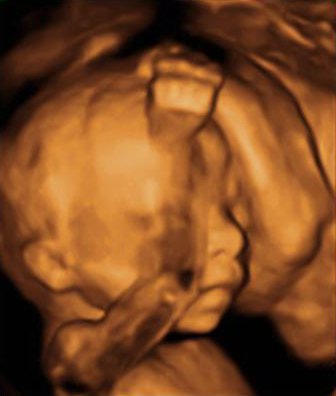

Con una edad gestacional de 20 semanas, este bebé está muy entretenido con un dedo en la boca. En esta ecografía de la semana 20, la morfológica, el especialista también mide el diámetro parietal del feto para comprobar su correcto desarrollo.

Cara y brazos de un feto de 20 semanas en ecografía 3D